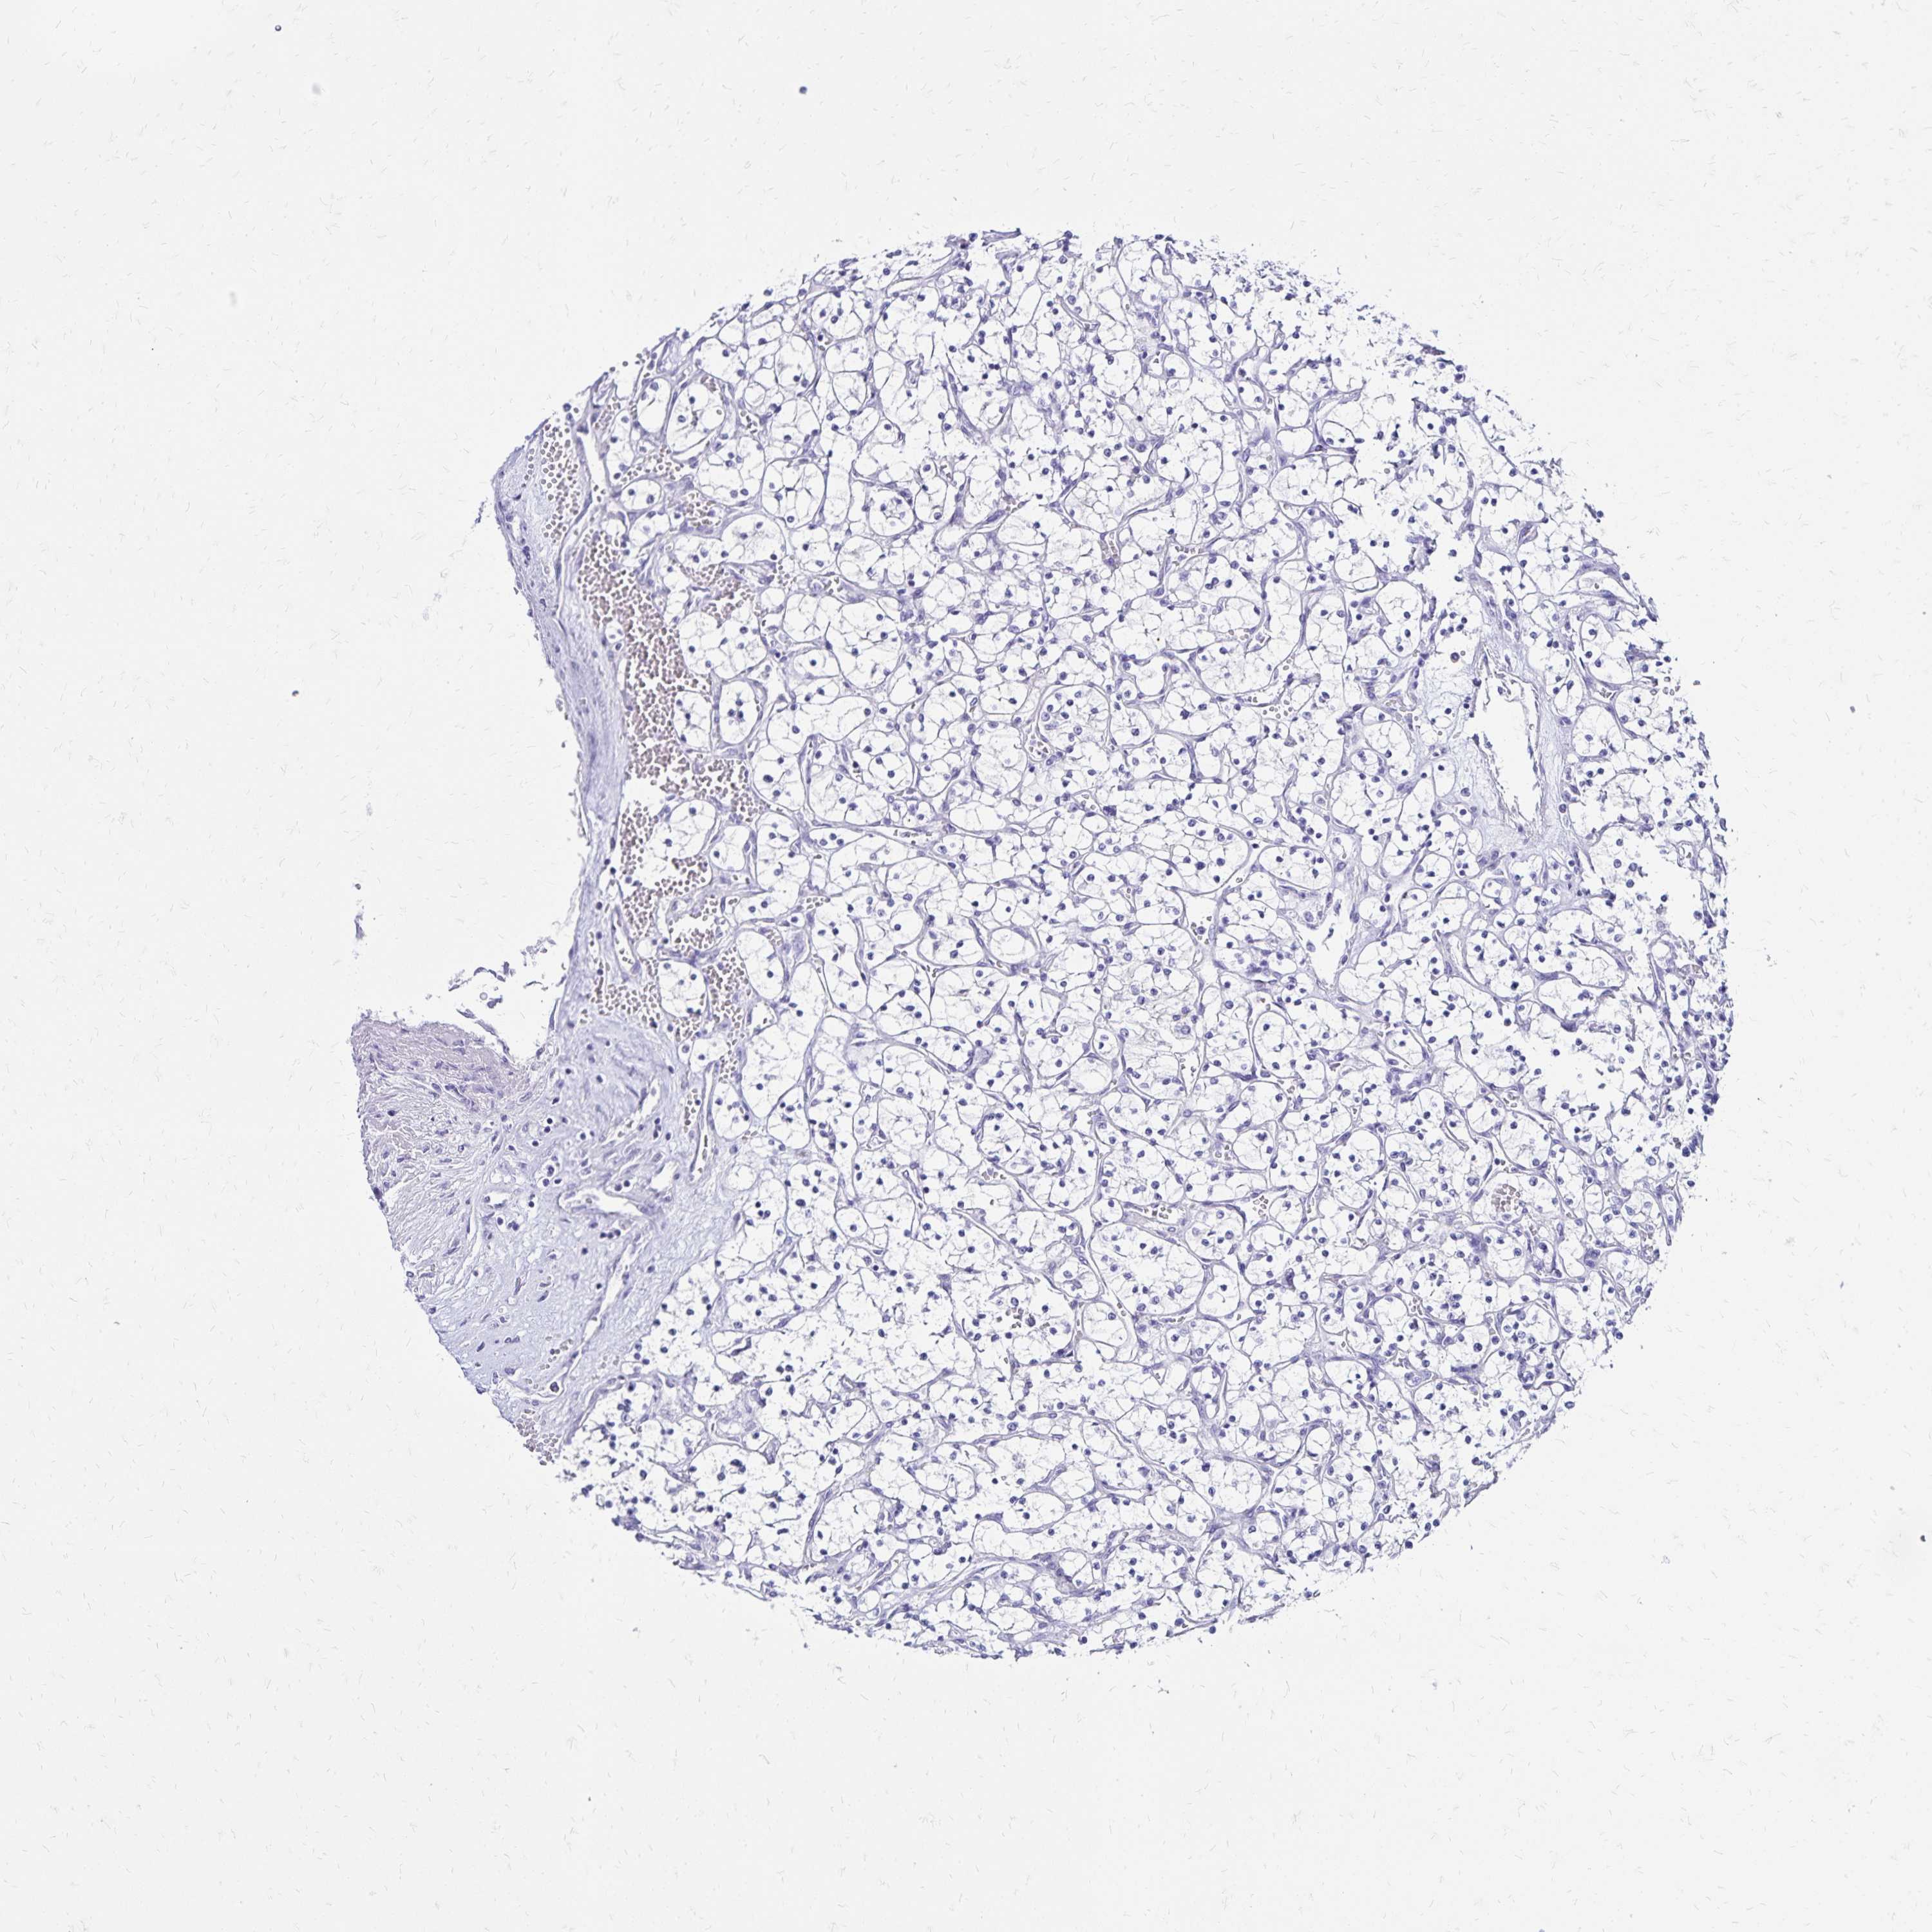

Renal cancer

Kidney chromophobe

KIDNEY CHROMOPHOBE (TCGA) - Interactive survival scatter ploti

The Survival Scatter plot shows the clinical status (i.e. dead or alive) for all individuals in the patient cohort, based on the same data that underlies the corresponding Kaplan-Meier plots. Patients that are alive at last time for follow-up are shown in blue and patients who have died during the study are shown in red.

The x-axis shows the expression levels (FPKM) of the investigated gene in the tumor tissue at the time of diagnosis. The y-axis shows the follow-up time after diagnosis (years). Both axes are complimented with kernel density curves demonstrating the data density over the axes. The top density plot shows the expression levels (FPKM) distribution among dead (red) and alive patients (blue). The right density plot shows the data density of the survived years of dead patients with high and low expression levels respectively, stratified using the cutoff indicated by the vertical dashed line through the Survival Scatter plot. This cutoff is automatically defined based on the FPKM cutoff that minimizes the p-score. The cutoff can be changed by dragging the vertical line or by entering a cutoff value in the square labeled "Current cut-off".

Under the Survival Scatter plot the p-score landscape (black curve; left axis) is shown together with dead median separation (red curve; right axis). Dead median separation is the difference in median mRNA expression between patients who have died with high and low expression, respectively. It is calculated as follows: median FPKM expression of dead patients with high expression - median FPKM expression of dead patients with low expression. This is intended to aid the user in visually exploring custom cutoffs and the associated p-scores and dead median separation.

Individual patient data is displayed and can be filtered by clicking on one or more of the category buttons on the top of the page. Categories describing expression level and patient information include: high, low, alive, dead, female, male and tumor stages. The scale of the x-axis can be toggled between linear and log-scale by clicking on the "x log" button. Mouse-over function shows TCGA ID, patient information and mRNA expression (FPKM) for each patient.

& Survival analysisi

Kaplan-Meier plots summarize results from analysis of correlation between mRNA expression level and patient survival. Patients were divided based on level of expression into one of the two groups "low" (under cut off) or "high" (over cut off). X-axis shows time for survival (years) and y-axis shows the probability of survival, where 1.0 corresponds to 100 percent.

CCDC39 is not prognostic in Kidney Chromophobe (TCGA)